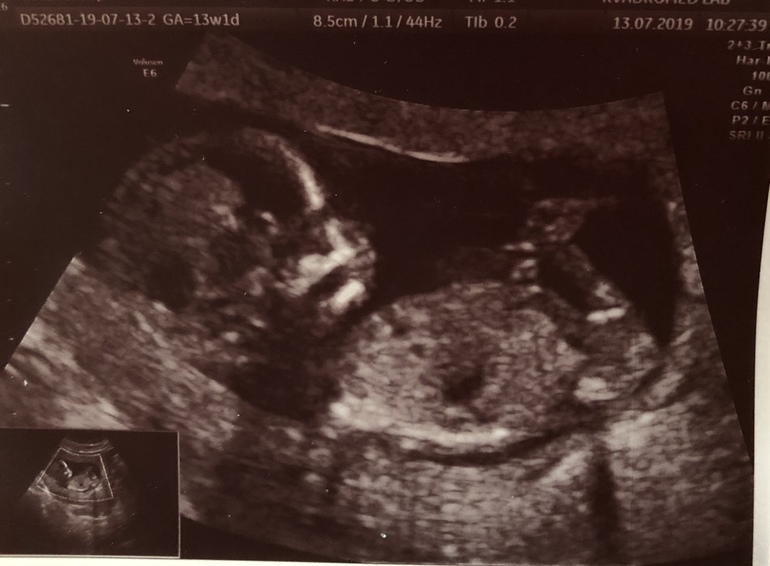

Пол малышабыли на узи вчера в 13,2 , скрининг. Все отлично, соответствует сроку до дня. А теперь вопрос про пол, действительно ли так много ошибок с определением на таком сроке, врач сказала, по половому бугорку предположительно девочка, и дала довольно маленький процент ошибки-10%. Тк первая девочка у нас, естественно муж хотел мальчика, и когда это озвучили, он не смог скрыть в глазах грусть-печаль. Естественно, ребёнок наш, пол не выбирают, что дано, то дано. Это всего лишь первые эмоции, и я это понимаю...

как тут вообще смотрят, скажите, профи?

на фото половой бугорок параллельно позвоночнику - девочка.

Нам узист также предположил 90% на первом скрининге, все подтвердилось.